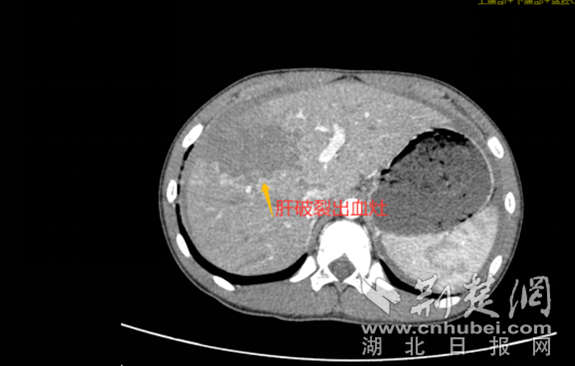

经过询问,涛涛告诉医生,两辆自行车相撞时,他的右上腹部被对方的自行车把手顶到过,还在隐隐作痛。出于专业敏感性,医生迅速给涛涛完善了胸腹部的增强CT,然而这一检查却让家属惊出一身冷汗。检查结果显示,涛涛肝脏破裂并腹腔积液、积血,如果肝部动脉出血不能控制,孩子可能因为失血性休克而危及生命,手术是首选治疗方案。

增强CT显示肝破裂出血灶 通讯员 供图